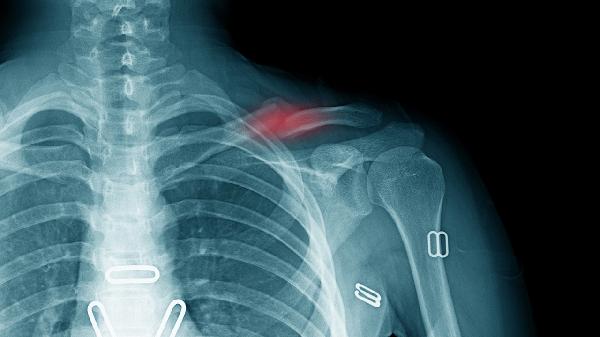

锁骨骨折保守治疗一般需要2000元到8000元,实际费用受到骨折类型、治疗方案、地区差异、复查频率、并发症处理等多种因素的影响。

单纯线性骨折仅需简单固定,费用约2000-4000元;粉碎性骨折或伴有移位的骨折可能需多次手法复位,费用可达5000-8000元。儿童锁骨骨折愈合快,通常费用低于成人。

基础保守治疗包括八字绷带固定约500-1000元和锁骨带固定约800-1500元。若需持续牵引治疗或定制支具,费用可能增加2000-3000元。中医正骨手法可能额外产生500-2000元治疗费。

三甲医院治疗费比社区医院高30%-50%,东部沿海地区费用普遍比中西部高20%-40%。医保报销比例影响实际支出,城乡居民医保通常可报销50%-70%基础治疗费用。

常规需3-5次X线复查每次约150-300元,若出现延迟愈合需增加复查次数。部分医院会包含1-2次康复评估约200-500元/次,高龄患者可能需额外骨密度检查约300元。

约15%患者会出现固定松动需重新处置增加500-1000元,皮肤压疮处理约需300-800元。若保守治疗失败转手术,前期费用不计入最终治疗成本。